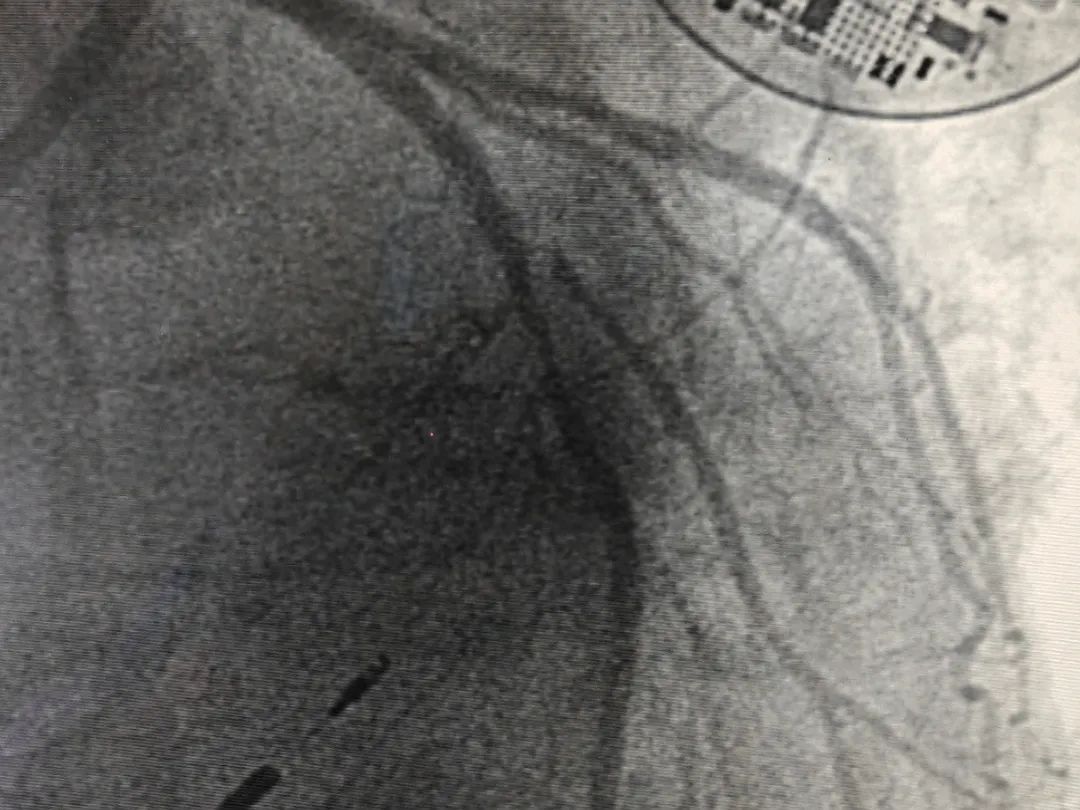

激光成形术前